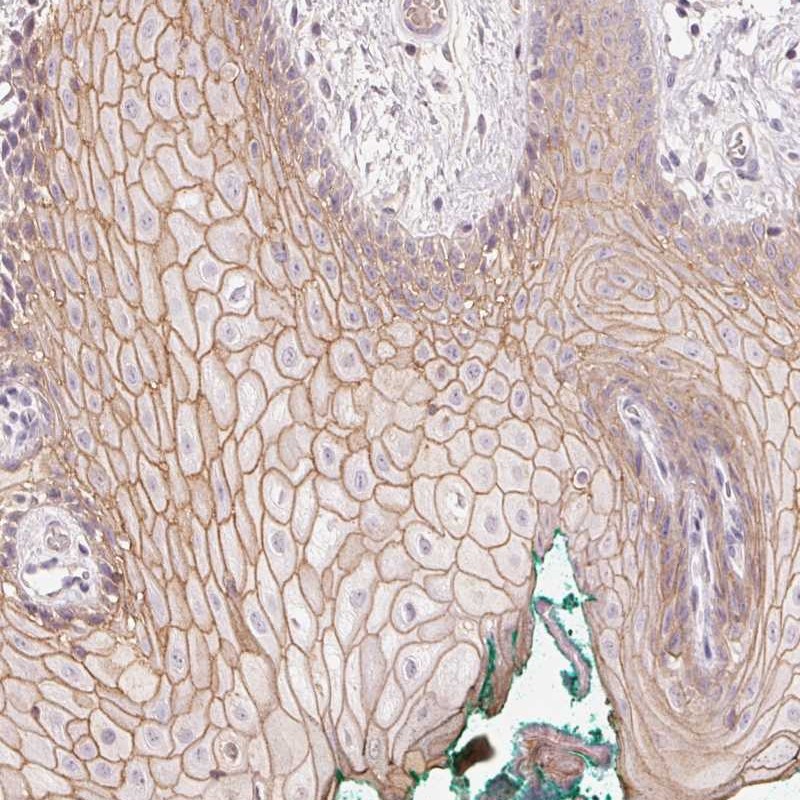

Immunohistochemical staining of human oral mucosa shows moderate membranous positivity in squamous epithelial cells.